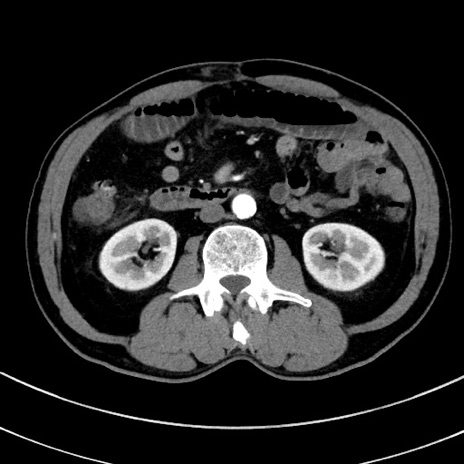

症例8(横断像)

【症例】 60歳代男性

【主訴】 黒色吐物

【現病歴】 4日前から嘔気自覚、2日前の朝食後にも嘔気あり、自分で手で嘔吐反射起こし嘔吐したところ血が混ざっていたため受診。

【既往歴】 5年前汎発性腹膜炎を伴う急性虫垂炎で手術、高血圧、前立腺肥大症、高脂血症

【身体所見】 腹部正中に手術癩痕あり 腹部平坦・軟圧痛なし膨満感あり

【データ】WBC 8400、CRP 4.54

冠状断像